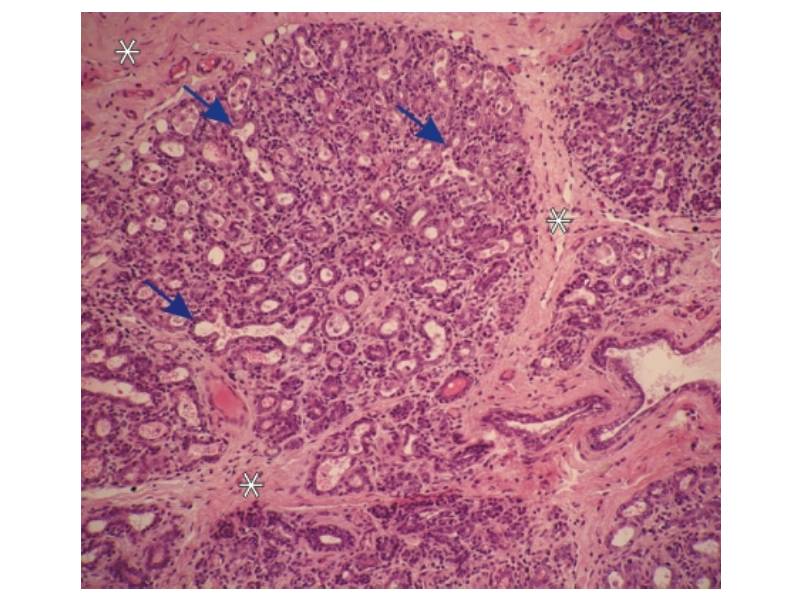

Mammary gland and digestive track

Histology